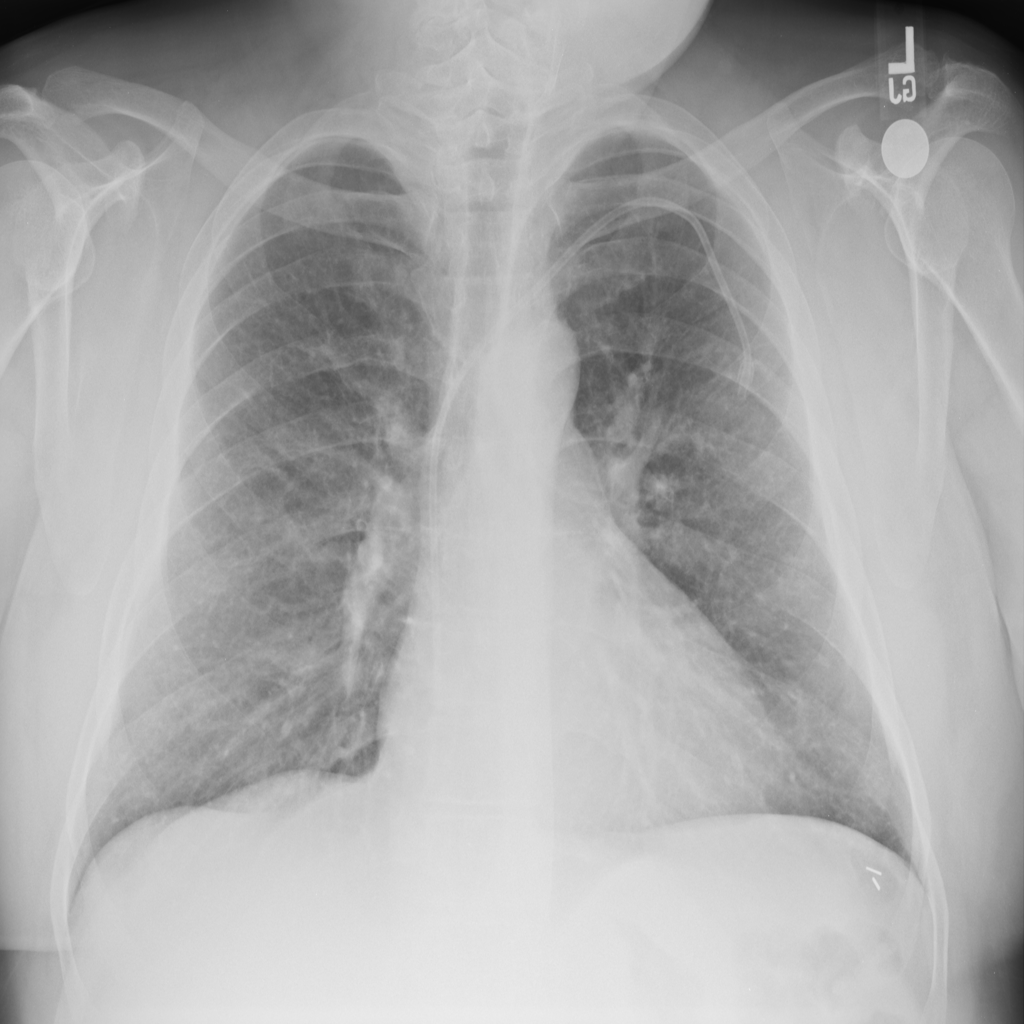

Cardiomegaly

Cardiomegaly means the heart appears enlarged on the chest X-ray. It is a descriptive imaging finding that can be related to heart strain, chronic pressure or volume changes, or even projection effects.

Showing up to 90 reference images for Cardiomegaly.

PAT-AE5C · IMG-000Cardiomegaly

PAT-AE5C · IMG-000

PA